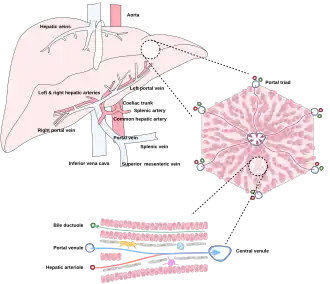

Microscopically, each liver lobe is seen to be made up of hepatic lobules. The lobules are roughly hexagonal, and consist of plates of hepatocytes, and sinusoids radiating from a central vein towards an imaginary perimeter of interlobular portal triads.[24] The central vein joins to the hepatic vein to carry blood out from the liver. A distinctive component of a lobule is the portal triad, which can be found running along each of the lobule's corners. The portal triad consists of the hepatic artery, the portal vein, and the common bile duct.[25] The triad may be seen on a liver ultrasound, as a Mickey Mouse sign with the portal vein as the head, and the hepatic artery, and the common bile duct as the ears.[26]

Histology, the study of microscopic anatomy, shows two major types of liver cell: parenchymal cells and nonparenchymal cells. About 70–85% of the liver volume is occupied by parenchymal hepatocytes. Nonparenchymal cells constitute 40% of the total number of liver cells but only 6.5% of its volume.[27] The liver sinusoids are lined with two types of cell, sinusoidal endothelial cells, and phagocytic Kupffer cells.[28] Hepatic stellate cells are nonparenchymal cells found in the perisinusoidal space, between a sinusoid and a hepatocyte.[27] Additionally, intrahepatic lymphocytes are often present in the sinusoidal lumen.[27]

Microscopic anatomy of the liver

Types of capillaries–sinusoid on right

Diagram of liver, lobule, and portal tract and their inter-relations